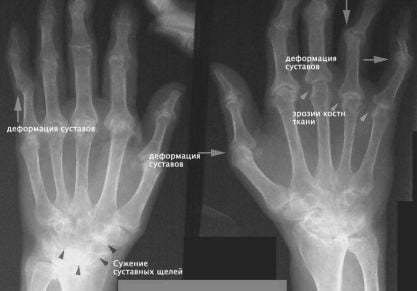

Кисть – это одна из самых функционально сложных частей тела. Ее особенностью является то, что она состоит из большого количества мелких костей и предназначается для выполнения тонких манипуляций. Обычно боль в кистях рук появляется после серьезной нагрузки, вследствие перелома, продолжительной работы за клавиатурой компьютера, растяжения. При этом болевые ощущения могут быть настолько сильными, что лишают человека возможности работать руками. Он даже не всегда может обслужить себя. Медлить с лечением такой боли не стоит, так как можно остаться инвалидом.